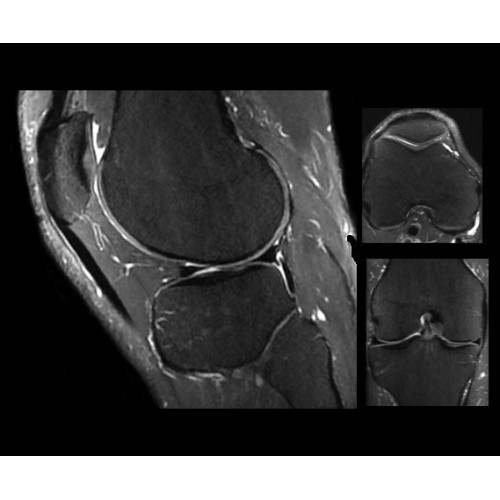

SIGNA PET/MR 3.0T — это гибридная система, в которой совмещаются две принципиально разные технологии — магнитно-резонансную томографию (МРТ) и позитронно-эмиссионную томографию (ПЭТ). Система отличающийся высокой чувствительностью и эффективностью и предназначена для диагностики в области онкологии, неврологии, кардио-васкулярных исследований, исследований воспалительных процессов.

Компания GE Healthcare представляет революционную, полностью интегрированную систему SIGNA PET/MR1, в которой сочетаются времяпролетная технология (TOF) и возможности напряженности магнитного поля 3.0 Тл. Мы поможем вам поднять исследования на более высокий уровень. SIGNA PET/MR позволяет достичь впечатляющей точности и скорости исследований, а благодаря новейшей технологии реконструкции Q.Clear2 качество изображений улучшается в два раза. Кроме того, в систему включен полный набор клинических приложений и гибких катушек для проведения любых видов исследования, открывая для вас возможности визуализации, о которых вы даже не догадывались.

Кроме того, в результате использования технологии TOF и инновационной технологии реконструкции Q.Clear вы сможете добиться прекрасного соотношения сигнал/шум. А благодаря технологии нулевого времени эхо (ZTE) визуализировать костную структуру без ионизирующего излучения. Все эти разработки для улучшения качества сканирования и точности анализа помогут вам использовать весь потенциал ПЭТ/МРТ.

• МРТ с функцией нулевого времени эхо (ZTE) отличается точностью, возможностью персональных настроек и отсутствием ионизирующего излучения. Она приходит на смену традиционному исследованию на основе рентгеновского излучения. МРТ с функцией нулевого времени эхо (ZTE) на базе SIGNA ПЭТ/МРТ является более надежной и быстрой по сравнению с системами, использующими сверхмалое время эхо (UTE).